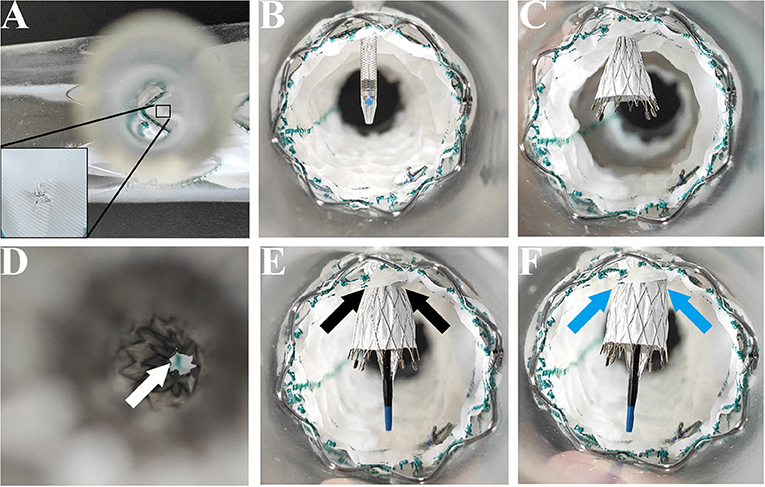

This part of this study was designed to assess the feasibility of the MCPF on stent grafts. The definition of successful procedure was that the delivery system of the branch stent came through the MCPF, then the branch stent was completely released, and flared with an angioplasty balloon.

The main stent grafts were 34 mm Valiant Thoracic Stent Grafts, which were generously donated by Medtronic Vascular, Santa Rosa, California, USA. All the 12 main stent grafts were released, prefenestrated with a 5 × 5 mm cross (Figure 1A), and then delivered into the silicone aortic models. There were 12 Fluency Plus Stents (Bard Peripheral Vascular, Tempe, Arizona, USA), in which the sizes were 7 × 60 mm (3 stent grafts), 8 × 40 mm (3 stent grafts), 12 × 80 mm (3 stent grafts), and 13.5 × 40 mm (3 stent grafts). The delivery system came through the fenestration (Figure 1B) and slowly released the stent grafts when tips passed 2–3 cm (Figure 1C). When the branch stents were completely released from the delivery system (Figure 1D), a 10 × 40 mm balloon (Mustang, Boston Scientific, Natick, Massachusetts, USA) was delivered to furtherly enlarge the orifice of the branch stents (Figures 1E,F).

Feasibility of the Prefenestration

There was no residual stenosis after balloon dilatation of the branch stents before the fatigue test. The MCPF can be easily flared by a balloon at 4–8 atmospheres (Supplementary Figure S1). After the fatigue test, minor residual stenosis was observed from an overhead view (Supplementary Figure S3D).

Morphological Analysis

After a 5-year simulated cardiac cycle, the structures of the main and branch stents were stable under light microscopy (Figures 4A–D). The fabrics around holes in each group were basically undamaged and remained connected under the light microscopy (Figures 4E–H). Figures 4I–L showed the SEM observation of fabrics around holes of each group, in which the organization was relatively tight. The membrane and metal structures were intact in the branch stents under the observation of SEM (Figures 4M–P).

Third, a 5 × 5 mm prefenestration on Valiant Stent Grafts then engaged with stent grafts was confirmed safety and integrity in a 5-year stimulated fatigue test and a median 38.9-month clinical follow-up. Although in-vitro experiment showed that a laser or needle effectively generated a hole in the membrane, the controllability was severely affected by the aortic pulsation in vivo (24, 27). The laser may cause serious damage to the membrane, which resulted in junction weakness and gutter leakage (27). In the fatigue test of this study, no obvious damage was found beyond the fenestration at 262,800,000 cardiac cycles. There was also no disconnection or dislocation between the main and branch stents found in the follow-up CTA. In summary, the MCPF might be more controllable in vivo and safer compared with the current in situ fenestration technique.